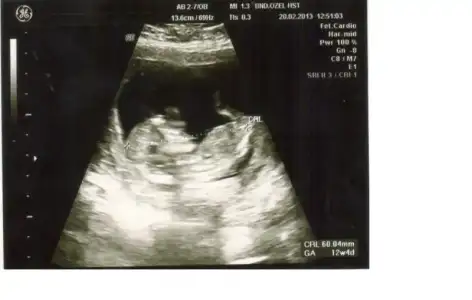

dr soylemeden siz gorun genital nub teorisi ( bebegin cinsiyeti)

benim bebişimede bakarmısınız.

Evt erkege benziyo ama kesinndediklerim kadar degil

hayır canım benim bir tane kızım var bu ikincisi, merak ettim ama ben nub göremedim, nubun olması gereken yerdeki uzantıyıda bacağa benzettim, bu kınulara biraz meraklıyım beni aydınlatırmısın nubmu bacakmı o, vede vakit ayırdığın için tşkr birde beni aydınlatırsan çok sevinirim..